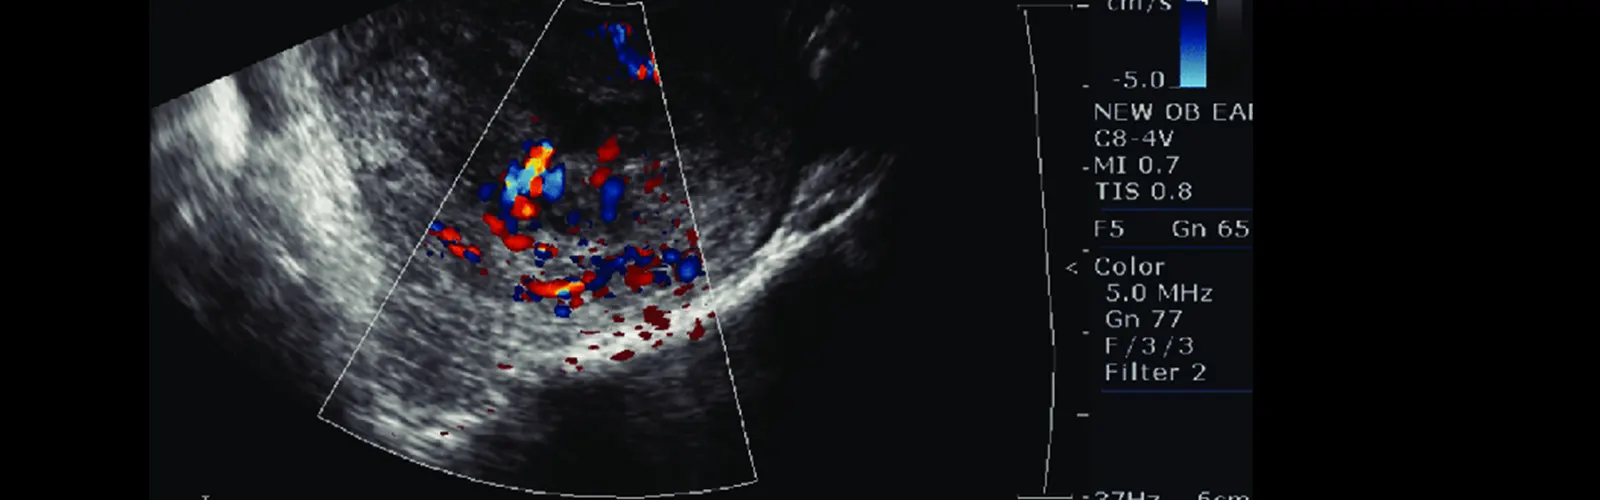

Color Doppler Ultrasound is a non-invasive imaging technique that uses sound waves to produce images of blood flow in the body. When applied to the pelvis, it can be used to evaluate.

The role of color Doppler ultrasound in the pelvis is to help diagnose and monitor conditions that affect blood flow in this area, such as:

Gynecological conditions: It can help evaluate conditions such as uterine fibroids, ovarian cysts, endometriosis, and adenomyosis by assessing the blood flow in the pelvic organs.

Pelvic pain: It can help identify the cause of pelvic pain by evaluating blood flow in the pelvic vessels and organs.

Pregnancy: It can be used to monitor fetal growth and development and to assess blood flow in the placenta.

Infertility: It can help identify abnormalities in blood flow to the ovaries or uterus that may be contributing to infertility.

Overall, color Doppler ultrasound is a valuable tool for evaluating blood flow in the pelvis and can aid in the diagnosis and management of various pelvic conditions.